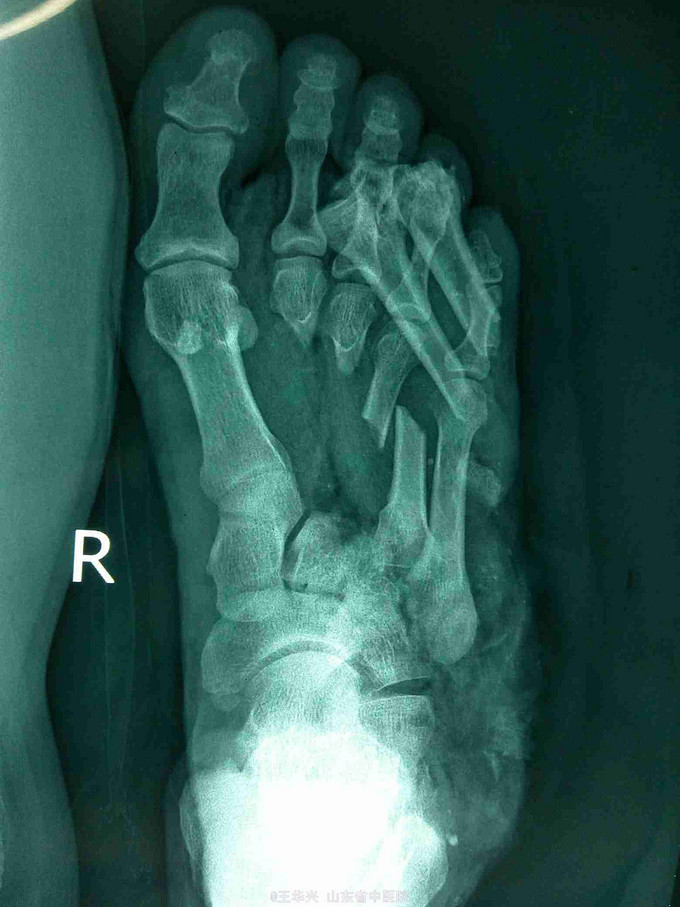

主诉:车祸致左足疼痛、活动受限并有大面积软组织损伤6小时。 现病史:患者6小时前因车祸致左足疼痛,活动受限伴有足背部大面积软组织损伤收住入院,急诊诊断为“左足毁损伤”。患者左足麻木感,大片足背软组织翻向外侧。

查体:左足疼痛,功能活动受限,伴有大面积软组织损伤,软组织向外侧翻转,足部前侧可见5*3cm软组织缺损,患处麻木感,足背动脉不可及。 辅助检查:x线 左足第2,3,4跖骨骨折